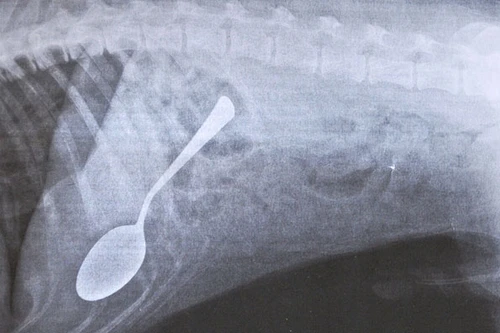

Chú chó sống sót khi nuốt phải thìa dài gần 18cm